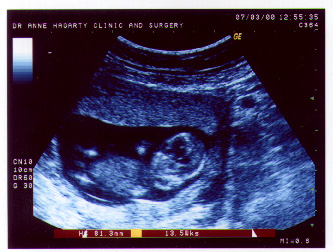

| And here he is just 2 weeks before his birth. |